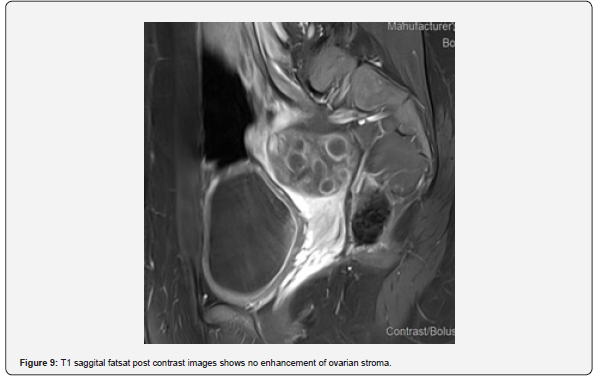

The patient is a 12-year-old girl who presented to emergency department with severe left-sided abdominal pain associated with persistent vomiting for the past two days. On physical examination left flank tenderness was noted with radiation to suprapubic area, there was no diarrhea or fever. Pelvic ultrasound with Doppler demonstrated bilaterally enlarged ovaries with small follicles with a markedly enlarged left ovary showing reduced vascularity and no evidence of identifiable ovarian cyst (Figures 1-4). Magnetic resonance imaging (MRI) demonstrated bilateral ovarian enlargement with multiple small follicles, assuming polycystic ovarian morphology. The left ovary was significantly enlarged, positioned posterior to the uterus and showed stromal edema with decreased post-contrast enhancement compared to contralateral side, findings consistent with ovarian torsion (Figures 5-10).

No definite ovarian cyst was identified on MRI. Mild free fluid was noted in the left adnexa. Patient underwent emergency laparoscopy and ovarian torsion was confirmed intraoperatively. Left ovary was found enlarged and torsed with two twists. A small ovarian cyst measuring approximately 2x2 cm was detected. Ovarian sparing laparoscopic detorsion of the left ovary was performed with cyst marsupialization. Patients were discharged on postoperative day 3 in stable condition. Follow-up visit in clinic after one week showed uneventful recovery. This case report highlights the importance of prompt diagnosis of ovarian torsion for timely surgical intervention even in absence of detectable cyst on imaging. aiming to preserve ovarian torsion and future fertility.